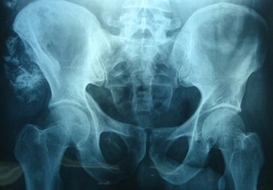

Leğen Kemiğinin Özellikleri